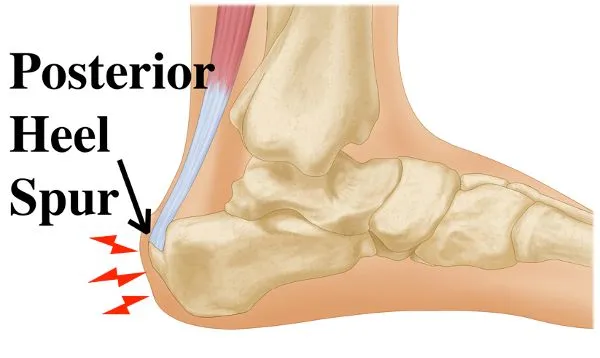

Posterior Heel Spur Diagnosed Treated by Foot Surgeons Mercy in Baltimore

Bone spurs of the heel of foot defined and treatments